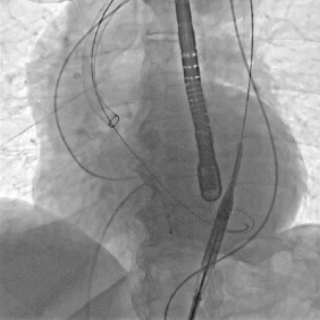

输送器在双重可调弯设计辅助下,精准操控,稳健过弓

输送器跨过瓣膜,可旋转定位件精准进入窦底